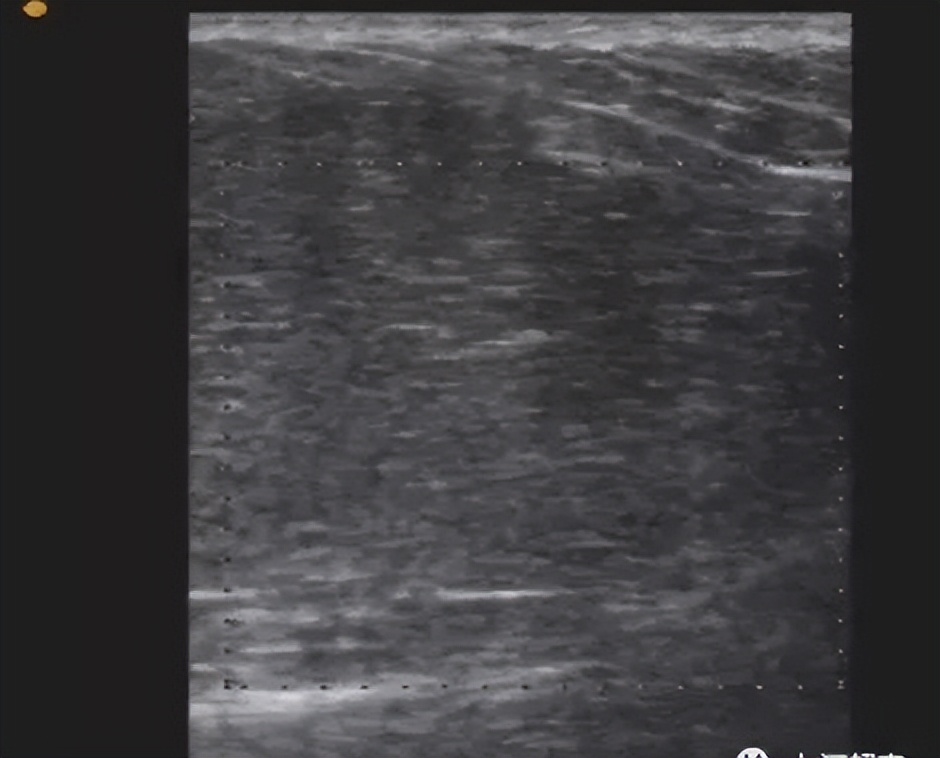

3. 副乳:发生率为1%~5% ,发生部位常见于腋窝或胸前部,多对称分布。可随着月经来潮而发生周期性的变化,妊娠期增大较明显,哺乳期可有泌乳。

超声表现:一般在表浅的皮下探及乳腺样组织,位置较表浅,呈薄片状。

小的副乳应和脂肪堆积鉴别

脂肪堆积表现为腋下皮下脂肪局部增厚,边界不清,与脂肪组织相连,按脂肪组织有规律排列;小副乳不按脂肪组织有规律排列,回声类似腺体组织回声。